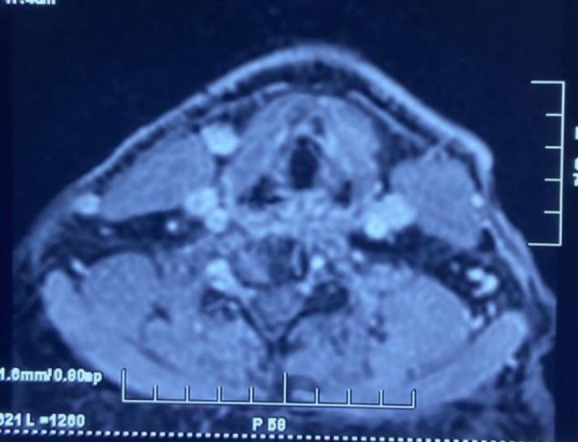

Introduction: Internal Jugular Vein (IJV) is an important landmark for Head and Neck surgeons during oncological clearance of disease from neck and microvascular reconstruction as well as for the intensivist during central line insertion. Detailed knowledge of the IJV anatomy and its variations is important to avert any catastrophic complications during surgery.

Materials and methods: Data of 350 patients was recorded prospectively and analysed over a period of two years and presence of IJV duplication was documented as percentages.

Results: A total of 350 patients with diagnosed oral cavity carcinoma were included who underwent neck dissection out of which seven patients were identified with Internal Jugular Vein duplication making it an institutional clinical prevalence of around 2%.

Conclusion: IJV duplication is inadvertently found intra operatively on maximum number of occasions therefore to avoid the risk of iatrogenic injury and undesired complications, preoperative imaging should be carefully assessed while planning the patient for surgery.